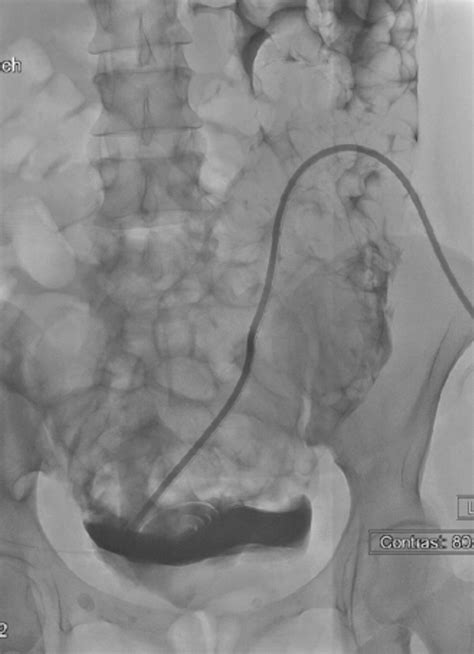

On the day of the Pd Catheter Placement, the procedure is performed in a sterile operating room environment. After anesthesia is administered—which may be local, regional, or general depending on the surgical approach—the surgeon creates a small incision. The catheter is carefully threaded into the peritoneal cavity, typically targeting the Pouch of Douglas, which is the lowest point in the abdominal cavity to ensure gravity-assisted drainage.

While most procedures are highly successful, patients should remain vigilant regarding potential issues. One common complication is catheter migration, where the tip of the tube moves out of the optimal position, causing drainage issues. Another concern is "one-way obstruction," where fluid flows in but fails to flow out, often due to omental wrapping—a condition where internal tissues wrap around the catheter tip.